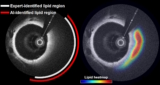

Artificial intelligence-based optical coherence tomography could improve long-term management of patients with coronary artery disease

Read article: Spectroscopic OCT plus AI detects high-risk plaque in coronary arteries

Read article: Spectroscopic OCT plus AI detects high-risk plaque in coronary arteries